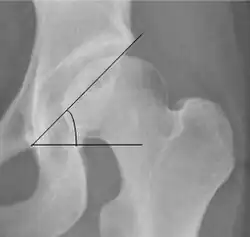

- (D) The acetabular index measures the acetabular roof slope. It is the most useful measure of acetabular dysplasia until 6 years of age. It is formed between Hilgenreiner line and the acetabular roof. In newborns, values of in males and in females are considered normal. It normally decreases with age: